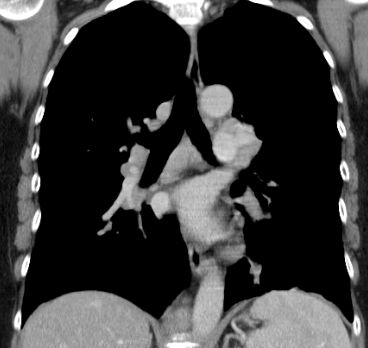

| Hilus- Lymphknoten | oft bihiläre Lymphadenopathie | 57-jährige Frau, die vor 15 Jahren ein Rektumkarzinom und vor einem Jahr ein Coecumkarzinom T4 N2b(14/14) Mo hatte. Beim Restaging vergrößerte Lymphknoten mediastinal, hilär beiderseits und paraaortal. Biopsie: floride Sarkoidose.![]() | |||||||||||||||||||||||||||||||||||||||||

| Lungen | mediastinale Lymphadenopathie | In 70% Lungeninterstitium befallen | Folge: Lungenfibrose. | ||||||||||||||||||||||||||||||||||||||||